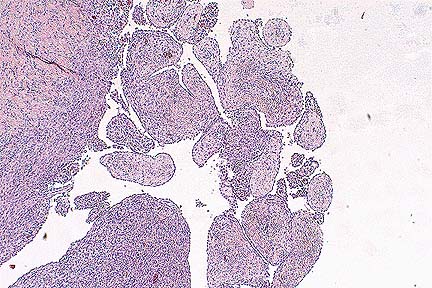

Papillary proliferations of neoplastic mesothelium in a Hanoverian gelding. (HE, 40X, 64K)

Gross Pathology: At necropsy, the subcutaneous tissue and all lymph nodes were severely edematous. The peritoneal cavity was filled with approximately 80 liters of a yellowish, clear fluid. The serosal surfaces of all abdominal organs, including the parietal peritoneum, were covered with numerous, gray-white, firm nodules ranging from 1 mm to 5 cm in diameter. The surface of the nodules was either smooth or cauliflower-like. There were no macroscopically visible masses in the abdominal lymph nodes. There were no gross or microscopic lesions in the thoracic cavity including lung, heart or pericardium.

Contributor's Diagnosis and Comments: Malignant biphasic peritoneal mesothelioma.

Histologically, the periphery of nodules consisted of epithelioid neoplastic mesothelial cells with squamous, cuboidal or columnar appearance forming papillary projections. In these cells, mitotic figures were frequent. Cells often sloughed from the surface of the nodules into the abdominal lumen. Occasionally, binucleated cells were observed. Inflammatory cells were diffusely scattered throughout the neoplastic tissue. The neoplastic nodules were well vascularized. The centers of the projections consisted of neoplastic mesothelial cells which were fibroblastic to mesenchymal in appearance. In some areas, there was an abundant accumulation of extracellular matrix.

Ultrastructurally, the cells in the periphery of the nodules had numerous microvilli and desmosomes. Within the nodules, neoplastic mesothelial cells were located in a collagen-rich matrix. The tissue had a sarcomatous appearance. These cells formed desmosomes as did the epithelioid neoplastic mesothelial cells in the periphery.

Peritoneal mesotheliomas are rarely seen in horses. In animals they are most frequent in cattle. Mesotheliomas arise from cells of mesodermal origin and grow in an epithelioid and mesenchymal pattern, as observed in the present case. The neoplasm must be classified as malignant because of its widespread occurrence on all abdominal serosal surfaces and the number of mitotic figures in the nodules. However, the tumor did not invade the underlying tissue and there was no metastasis to regional lymph nodes. Human mesotheliomas are classified as epithelial, sarcomatous and biphasic (mixed) depending on the predominant histological feature. In the present case, both epithelial and mesenchymal characteristics were observed. The tumor was, therefore, classified as malignant biphasic peritoneal mesothelioma.

AFIP Diagnosis: Serosal surface and attached skeletal muscle: Mesothelioma, Hanoverian, equine.

Conference Note: Mesotheliomas occur with the greatest frequency in cattle and dogs, but have been reported in most domestic species. In cattle, they occur most often as a congenital neoplasm in fetuses or young calves. Mesotheliomas arise from the serous lining of pericardial, pleural, and peritoneal cavities. They routinely spread by direct extension, regularly invade underlying tissue, but rarely metastasize to other organs; when dissemination does occur, it appears to be hematogenous. Mesothelioma arising from the tunica vaginalis is one of the most common tumors of the male Fischer 344 rat.

Grossly, mesotheliomas appear as multiple firm, sessile, or pedunculated nodules arising from a serosal surface. The nodules range in size from a few millimeters to 10 centimeters in diameter. The tumors may cause the accumulation of large amounts of fluid, resulting in ascites, cardiac insufficency, cardiac tamponade, or respiratory distress depending upon the location of the tumor. Adhesions are often formed between the affected serosal surface and adjacent organs.

Histologically, mesotheliomas exhibit a broad spectrum of patterns from mostly epithelioid to predominantly fibrous. The most common pattern consists of neoplastic cuboidal epithelioid cells covering papillary projections of neoplastic spindle cells which form a fibrovascular core. The fibrovascular core may appear sarcomatous and contains an extracellular matrix that is weakly metachromatic with Alcian blue, methyl violet, or toluidine blue stains. The metachromatic staining is lost after digestion with testicular hyaluronidase; therefore, the material is most likely hyaluronic acid. Ultrastructurally, neoplastic mesothelial cells have a prominent basal lamina, well developed microvilli, desmosomes, abundant rough endoplasmic reticulum, and mitochondria. Immunohistochemical staining is positive for keratin and sporadically positive for vimentin.